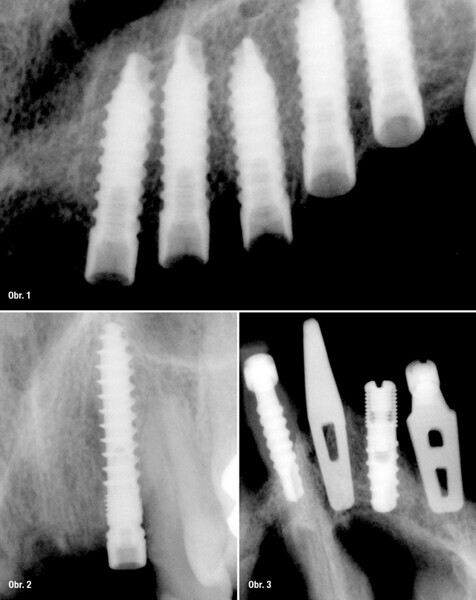

UIS Impladenta – Užití ve všech případech!